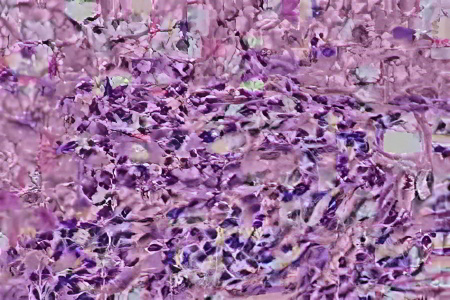

Диагностика заболевания основывается на серологических, биохимических и гистологических маркерах. Методы визуализации, такие как УЗИ и МРТ печени, не играют значительной роли в установлении диагноза.

Окончательное подтверждение диагноза осуществляется на основании биопсии печени. Гистологическое исследование должно показать наличие ступенчатых или мостовидных некрозов тканей, а также лимфоидную инфильтрацию (скопление лимфоцитов).